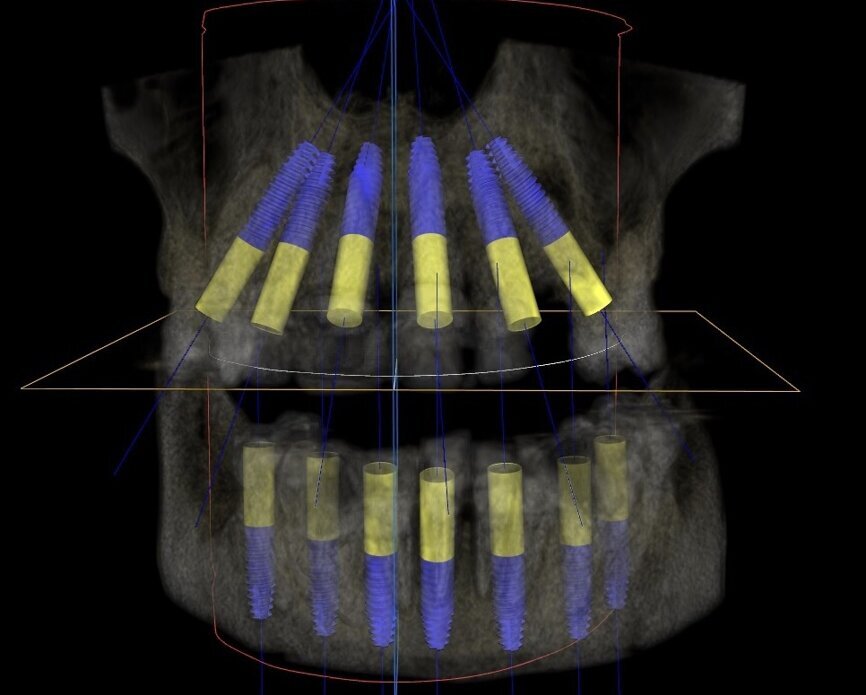

A CBCT scan and panoramic radiograph using the CS 8100 3D (Carestream Dental; Figs. 4 & 5) was taken to accurately capture the information needed to properly plan treatment for this case to ensure the most ideal outcome, especially since the patient had discussed his frustration with previous treatment that did not last very long or address his primary needs or requests. Using CS 3D Imaging Software (Carestream Dental), dental implants were virtually planned in key positions in both arches (Fig. 6).

A 3D virtual treatment plan was further developed from our planning with CS 3D Imaging Software, integrating it with the photographs and models with the assistance of 3D Diagnostix (3DDX; Fig. 9). A virtual online integrative meeting with 3DDX allowed for a comprehensive review of the assembled digital and clinical information to formulate an optimal treatment plan that would fulfil the necessary requirements for aesthetics, form and function.